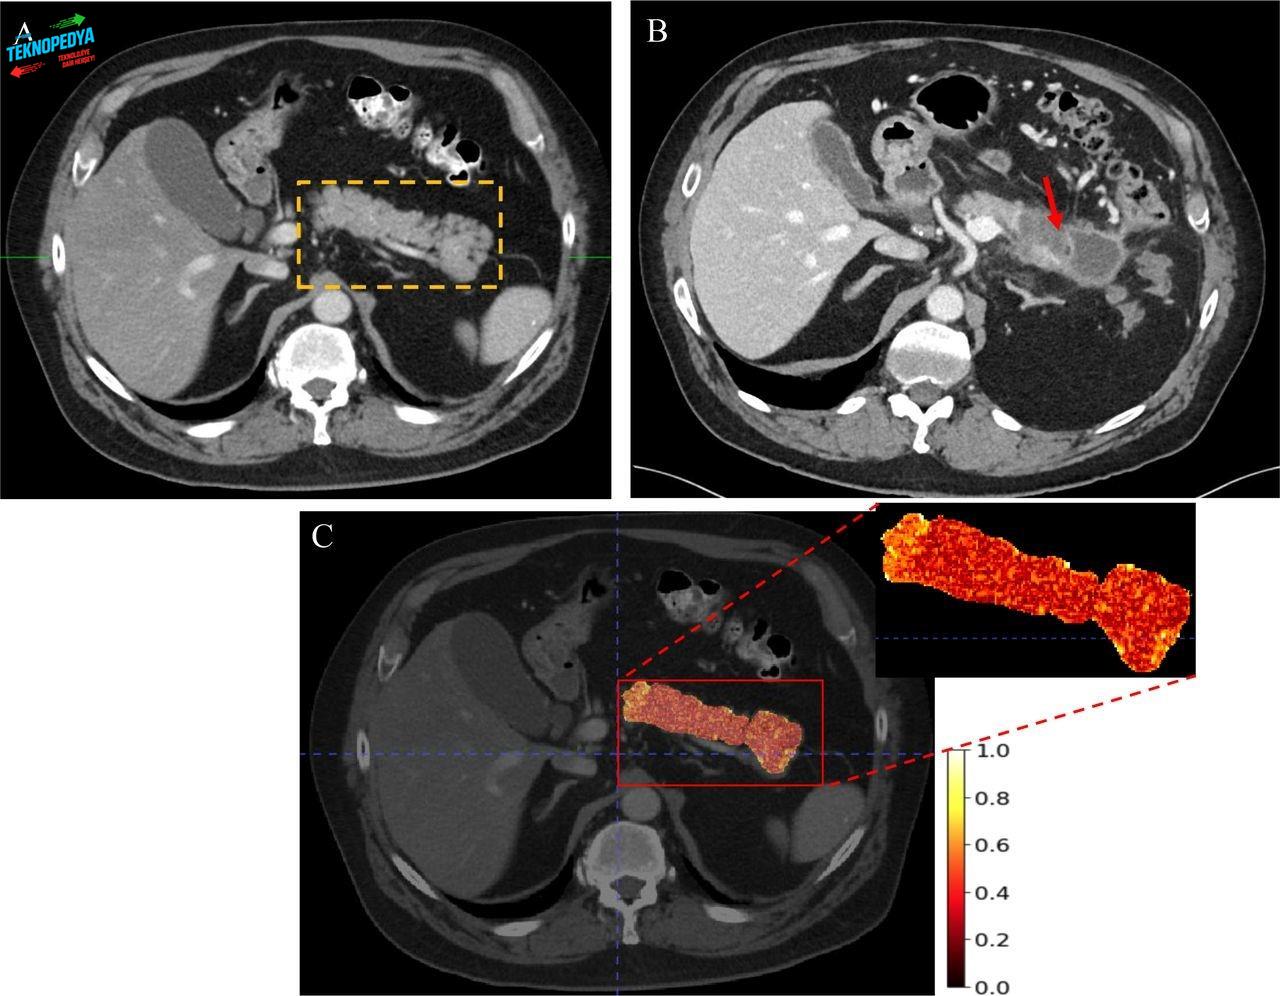

Araştırmada kullanılan yapay zeka sistemi “REDMOD” olarak adlandırılıyor. Bu model, standart BT taramalarında yer alan ancak radyologlar tarafından fark edilmesi zor olan mikroskobik desenleri analiz ediyor. Sistem, 1.400’den fazla bireyin görüntüleriyle eğitildi ve test edildi. Bu veri seti içinde, daha önce normal olarak değerlendirilen taramalara sahip ancak sonradan pankreas kanseri teşhisi konan 219 hasta da yer aldı. Yapılan karşılaştırmalarda yapay zekanın performansı dikkat çekici seviyede yüksek çıktı. Redmod, vakaların yüzde 73’ünü doğru şekilde tespit ederken aynı görüntüleri inceleyen radyologların başarı oranı yüzde 39’da kaldı. Tanıdan iki yıldan daha uzun süre önce çekilmiş görüntülerde ise fark daha da belirginleşiyor. Yapay zeka, yüzde 68 doğruluk sağlarken uzmanların oranı yüzde 23’te kaldı.

Modelin başarısı farklı hastaneler ve farklı görüntüleme cihazları arasında da tutarlılık gösterdi. Ayrıca, kanser gelişmeyen bireylerin taramalarının yüzde 80’den fazlasını doğru şekilde “negatif” olarak sınıflandırması sistemin yanlış alarm oranının da kontrol altında olduğunu ortaya koydu.